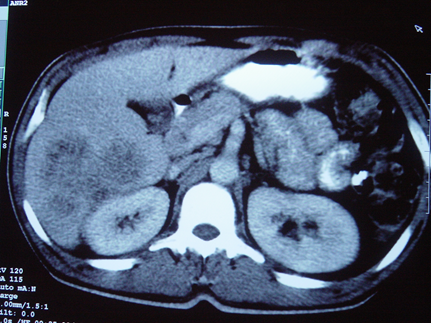

PVT diaqnozunu dəqiqləşdirmək üçün portoqrafiya aparılır – Doppler USM, KT və ya MRT angioqrafiya.

- Kontrastlı müayinələrdə damarda tromb və ya kavernoz transformasiya

Portoqrafiya – Doppler USM, KT və ya MRT angioqrafiya;

- portoqrafiyada vena mənfəzində trombun görünməsi;

- venanın distalında genişlənmə və kavernoz transformasiyanın görünməsi;